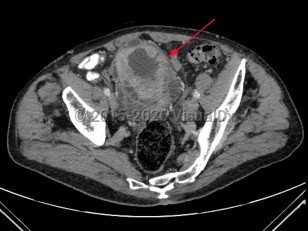

Rectal carcinomaRectal carcinoma

Ovarian cancerOvarian cancer